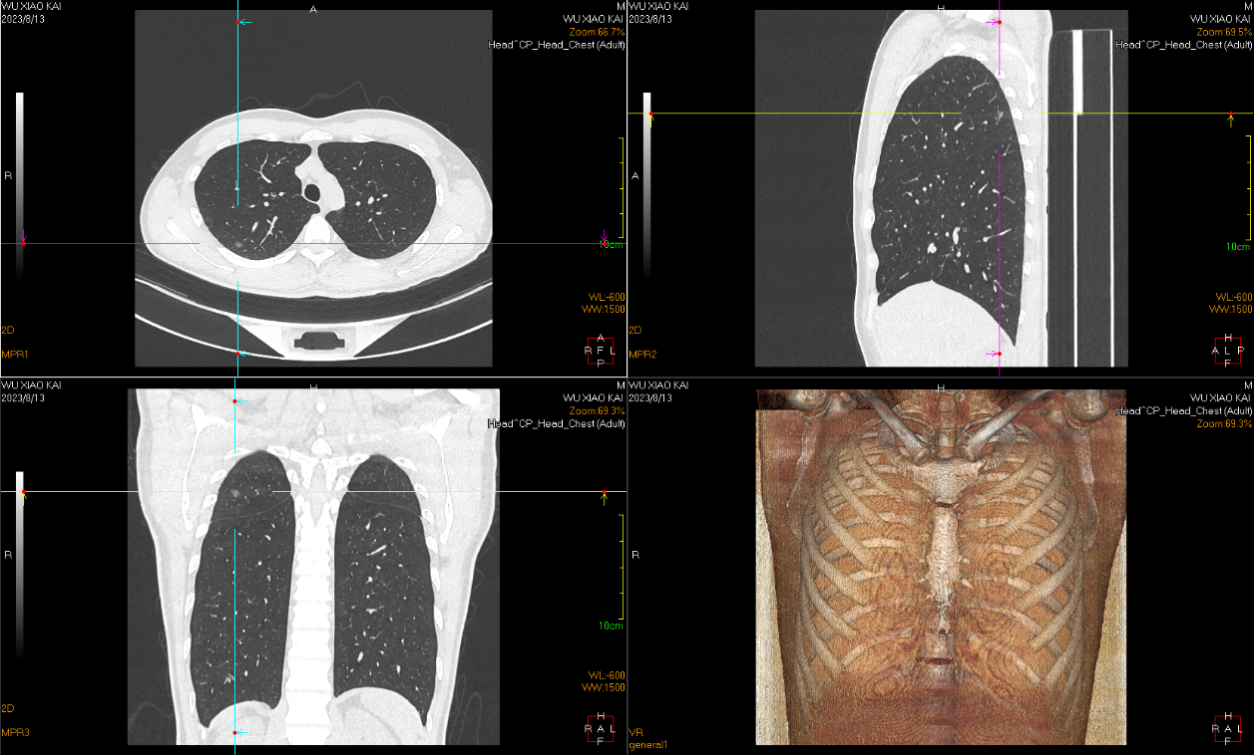

术前胸部CT